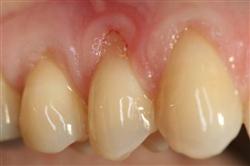

Normally gum tissue surrounds and protects the delicate roots of your teeth. Exposed tooth roots are prone to tooth decay, root canals, discoloration and actual jawbone loss. All of this can lead to tooth loss in advanced cases.

Functional Soft Tissue Grafting replaces the missing gum tissue and protects your teeth. For this reason, soft tissue grafting may be recommended even for back teeth.